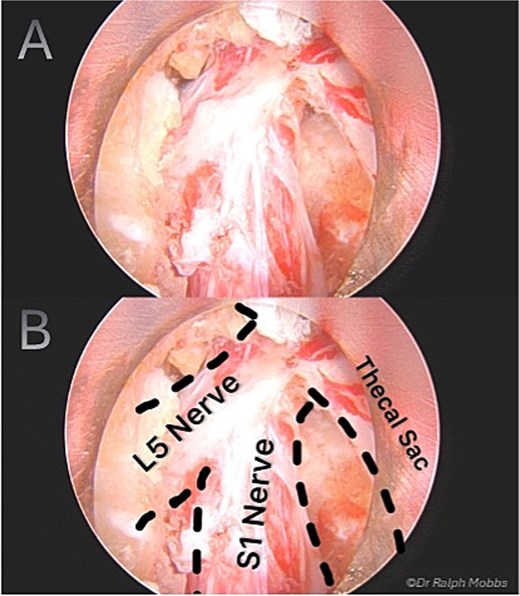

During endoscopic decompression of the left L4–L5 lateral recess, a type 2B conjoined L5 nerve root was identified sharing a common dural sleeve with the adjacent traversing nerve root. The neural elements were meticulously decompressed under direct high-definition visualization (Figs 2 and 3).

Intraoperative endoscopic view of L5 nerve duplication in the L4/5 lateral recess.

Endoscopic decompression at the left L5–S1 level unexpectedly revealed a type 1A CNR involving both the L5 and S1 roots (Fig. 5), which were found to be emerging from a shared dural origin (Fig. 6).

Intraoperative endoscopic view of conjoint L5 and S1 nerve root emerging from a shared dural origin.